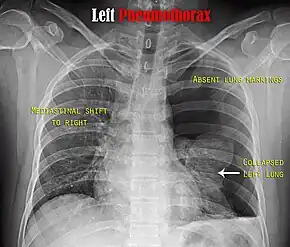

| A large right-sided spontaneous pneumothorax (left in the image). An arrow indicates the edge of the collapsed lung | |

Chest X-ray

A plain chest radiograph, ideally with the X-ray beams being projected from the back (posteroanterior, or "PA"), and during maximal inspiration (holding one's breath), is the most appropriate first investigation.[25] It is not believed that routinely taking images during expiration would confer any benefit.[26] Still, they may be useful in the detection of a pneumothorax when clinical suspicion is high but yet an inspiratory radiograph appears normal.[27] Also, if the PA X-ray does not show a pneumothorax but there is a strong suspicion of one, lateral X-rays (with beams projecting from the side) may be performed, but this is not routine practice.[14][18]

It is not unusual for the mediastinum (the structure between the lungs that contains the heart, great blood vessels and large airways) to be shifted away from the affected lung due to the pressure differences. This is not equivalent to a tension pneumothorax, which is determined mainly by the constellation of symptoms, hypoxia, and shock.[13]

The size of the pneumothorax (i.e. the volume of air in the pleural space) can be determined with reasonable accuracy by measuring the distance between the chest wall and the lung. This is relevant to treatment, as smaller pneumothoraces may be managed differently. An air rim of 2 cm means that the pneumothorax occupies about 50% of the hemithorax.[14] British professional guidelines have traditionally stated that the measurement should be performed at the level of the hilum (where blood vessels and airways enter the lung) with 2 cm as the cutoff,[14] while American guidelines state that the measurement should be done at the apex (top) of the lung with 3 cm differentiating between a "small" and a "large" pneumothorax.[28] The latter method may overestimate the size of a pneumothorax if it is located mainly at the apex, which is a common occurrence.[14] The various methods correlate poorly, but are the best easily available ways of estimating pneumothorax size.[14][18] CT scanning (see below) can provide a more accurate determination of the size of the pneumothorax, but its routine use in this setting is not recommended.[28]

Not all pneumothoraces are uniform; some only form a pocket of air in a particular place in the chest.[14] Small amounts of fluid may be noted on the chest X-ray (hydropneumothorax); this may be blood (hemopneumothorax).[13] In some cases, the only significant abnormality may be the "deep sulcus sign", in which the normally small space between the chest wall and the diaphragm appears enlarged due to the abnormal presence of fluid.[15]